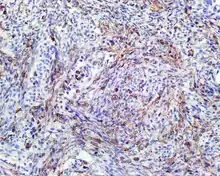

A high-power view of a hematoxylin- and eosin-stained slide showing respiratory epithelial inclusions within a spindled cell neoplasm showing characteristics of a biphenotypic sinonasal sarcoma

Hematoxylin and eosin stained image of a biphenotypic sinonasal sarcoma

• Infiltrative, highly cellular spindled cell neoplasm is poorly circumscribed and unencapsulated. Bone destruction or invasion is common. The cells show medium to long fascicles (nerve fibers), with a herringbone pattern. The cells are remarkably uniform with elongated nuclei. Delicate strands of intercellular collagen without ropy or dense deposition are seen. A very characteristic concurrent surface-type respiratory epithelial proliferation is found from the surface or in small cystic spaces around the cancer cells, often forming glands. The background may have a rich vascularity and usually has a small number of scattered lymphocytes. Extra growths or mitoses are rare, while necrosis, ulceration, and hemorrhage are usually absent.